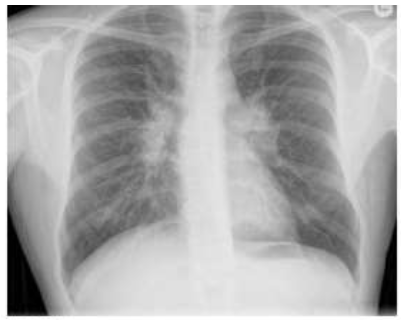

Na radiologia torácica há um achado clássico denominado de Tríade de Garland ou sinal do 1,2,3. (figura abaixo). Esses achados se referem ao alargamento mediastinal (paratraqueal direita, normalmente) e hilar bilateral (gânglios hilares).

Qual o diagnóstico etiológico?